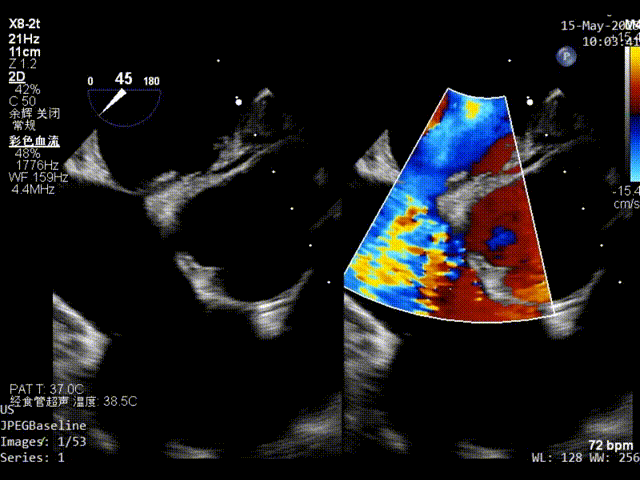

双房切面超声影像

静息状态下房水平见左向右分流。

color超声影像